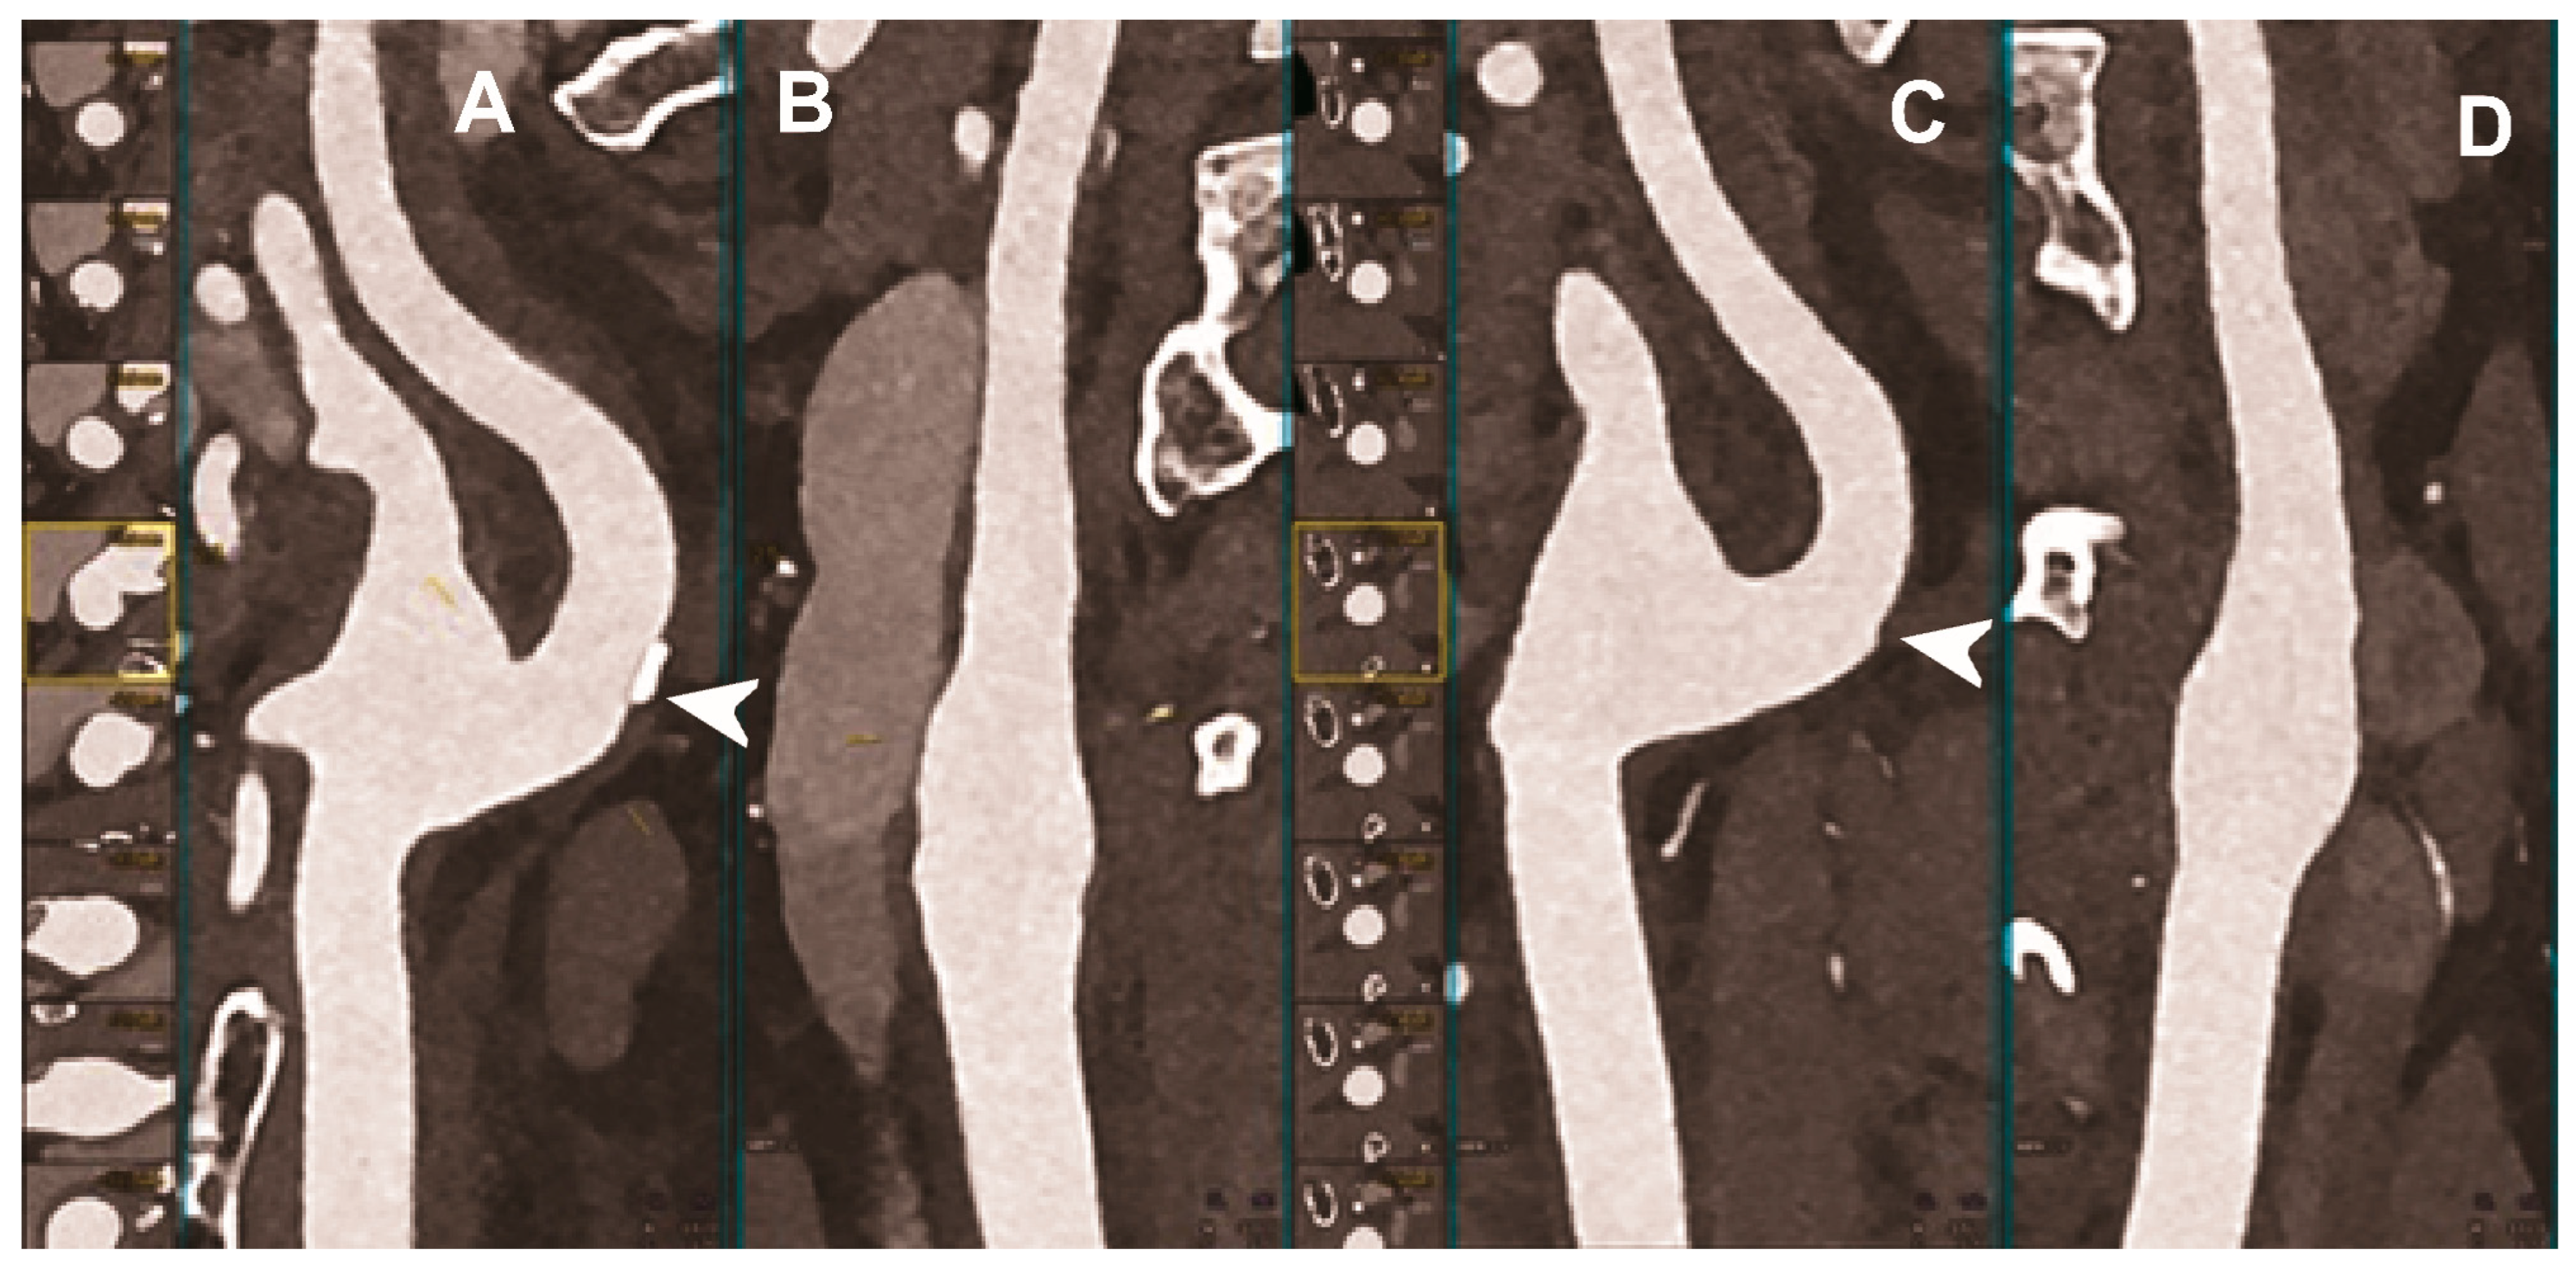

| Dangelmaier et al. 2018 [111] | In vitro phantom (abdominal aortic aneurysm phantom filled with iodine, gadolinium, or calcium). | Ability of PCCT in combination with a dual contrast agent injection to capture endoleak dynamics and effectively distinct leaking contrast media from intra-aneurysmatic calcifications, thereby allowing for a significant reduction of radiation exposure. |

| Sigovan et al. 2019 [112] |